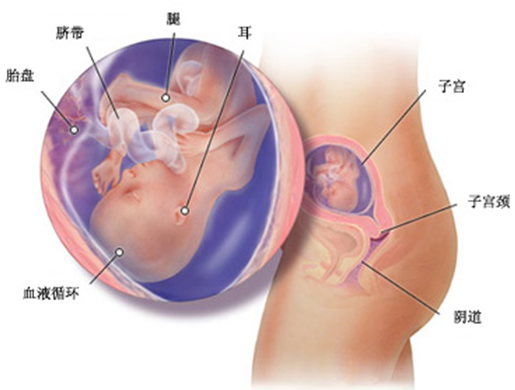

现在胎儿的身长达到 13 厘米,体重达到 170 克。这个星期胎儿已有一只梨子那么大,循环系统、尿道等也开始工作,胎儿开始平稳地吸入和呼出羊水,他(她)的肺正在发育得更强壮,以利于将来适应子宫外的空气。

从 16 周到 19 周,胎儿的听力形成,此时的胎儿就象一个小小“窃听者”,他(她)能听到妈妈心脏跳动的声音、大血管内血液流动的声音、肠蠕动的声音,他(她)最爱听妈妈温柔的说话声和歌声,因此孕中期是进行胎教的最佳时期。现在你可以和丈夫一起对胎儿进行胎教,有意识地与他(她)对话沟通,适当地抚摸腹部,为胎儿做做体操,与胎儿聊聊天,看一些美丽的图片,听听古典音乐,胎儿在温馨的母爱关怀下会健康地成长发育。

现在胎儿开始频繁地胎动了,在这一周,胎儿原来偏向两侧的眼睛开始向前集中。胎儿的骨骼差不多已成为类似橡胶的软骨,并开始逐步硬化。胎儿的身长已经接近 14 厘米,体重大约 200 克。